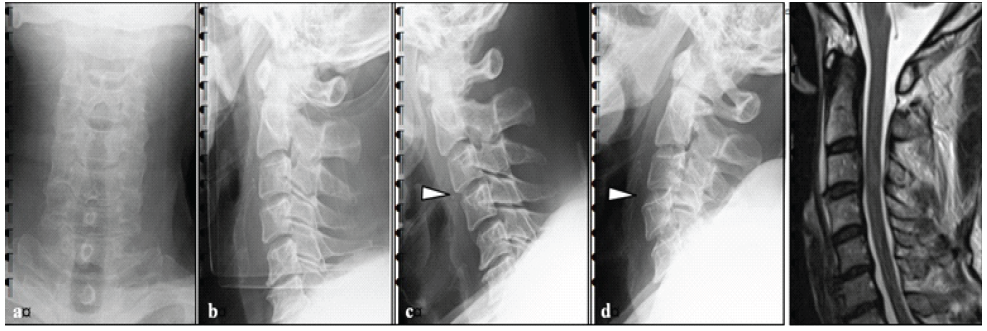

The patient was a 75-year-old male with no previous medical history. He fell off his bicycle while riding. He bruised his forehead and subsequently experienced neck pain and tetraplegia. Therefore, he was transported to a hospital by ambulance. X-ray imaging showed instability in the intervertebral space of the third/fourth cervical vertebrae (C3/4). Magnetic resonance imaging showed a T2 high-signal intensity area within the spinal cord at the C3/4 level (Fig. 1). He had severe muscle weakness and sensory disturbance, particularly on the right side (Table 1). No abnormal reflexes, such as deep tendon hyperreflexia or Babinski reflex, were noted (Table 2). The Japan Orthopaedic Association (JOA) score, which assesses physical dysfunction and the severity of myelopathy [12], was 1.5/17 points (Table 3). He was diagnosed with a cervical SCI (American Spinal Injury Association [ASIA] impairment scale C, Frankel grade C1) with C3/4 disc injury.

Figure 1: Pre-operative imaging findings. (a and b) There was no obvious vertebral fracture, but mild swelling of the retropharyngeal space. (c and d) Flexion and extension imaging of the cervical spine showed C3/4 instability. (e) MRI imaging showed a T2 high signal of the spinal cord on the C3/4 disc level.